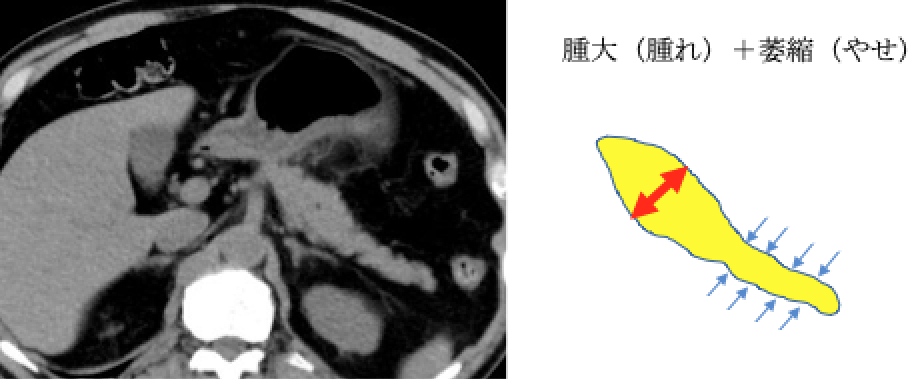

④ 膵腫大、萎縮

膵臓がんはすい管(消化液〈=すい液〉の通り道)から発生する膵管がんと言われています。 膵臓がんを発症すると、すい管が狭くなり、膵液が停滞します。その際に、主膵管拡張・膵のう胞(分枝膵管拡張)・脂肪変性(膵臓の凹みや痩せ)・腫れといった変化を引き起こします(膵臓がんの間接所見)。これにともなって、膵臓の炎症を起こしたり(みぞおちの痛み)、膵臓のはたらきが低下します(糖尿病の発症や悪化、味覚の変化、下痢など)。顕微鏡レベルの膵臓がん(上皮内がん)でも上記の間接所見や症状を伴うものがあることがわかってきました。膵臓がんが発生してから転移するまで約7年かかると言われております。この間に膵臓の形や膵管の変化をとらえることで早期の膵癌が発見できる可能性があります。

お腹や胸のCTを撮影したことのある人は膵臓に上記のような変化がないか主治医の先生に確認してもらいましょう。CTを何度か撮影したことがある人は比較してもらいましょう。胸のCTにも膵臓は一部うつっていることが多いです。